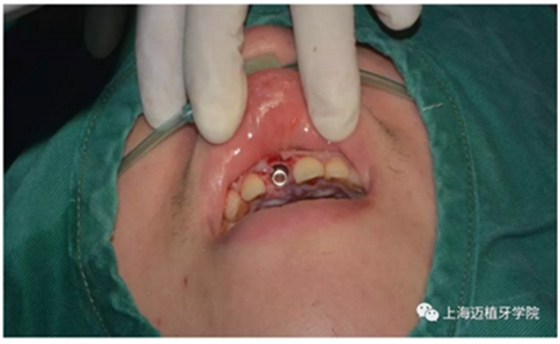

拔除殘根切開翻瓣

植入植體DTS:4.1*10 15A042/0061